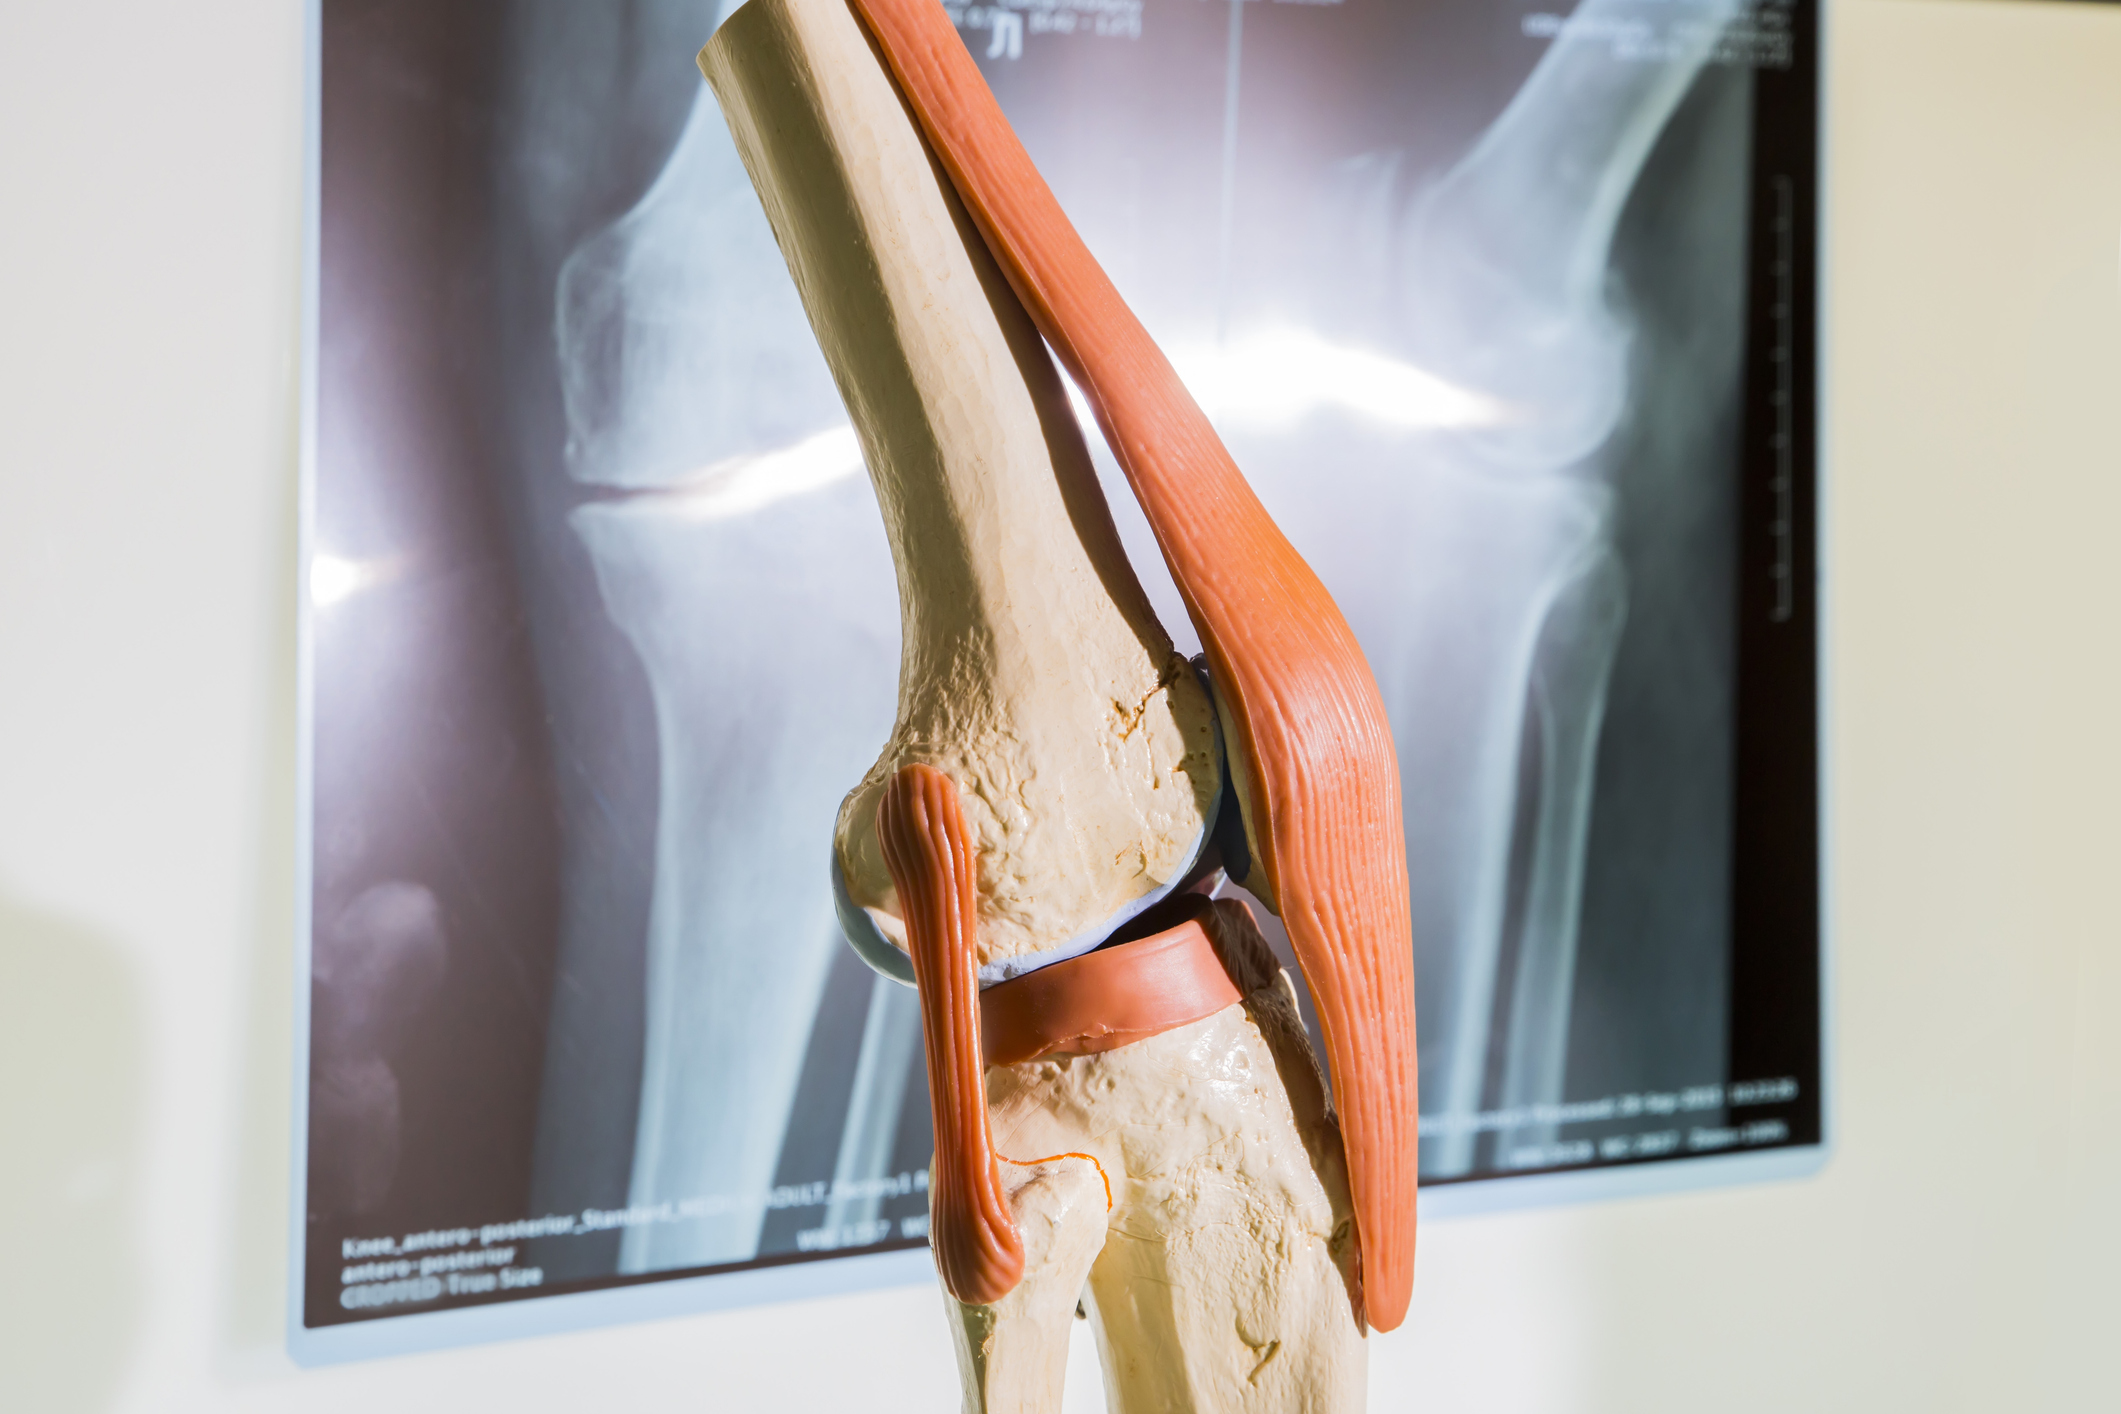

Le genou est une articulation complexe très mobile dans les 3 plans de l’espace. C’est une articulation portante soumise à des contraintes importantes dans la vie quotidienne notamment le poids du corps.

L’arthrose débutante interne est l’usure du cartilage présent entre le fémur et le tibia de la partie interne du genou . La morphologie du membre inférieur en est souvent la cause principale. Sur une forme en Genu Varum, tout le poids du corps passe par cette partie interne du genou entraînant une usure prématurée du cartilage et du ménisque.

L’ostéotomie tibiale de valgisation vise à corriger l’axe du membre inférieur. Cette correction est faite par une section partielle du tibia juste en dessous de l’articulation du genou en zone métaphysaire.

L’os du tibia est alors partiellement sectionné à la scie, en laissant une partie intacte externe qui va réaliser une charnière osseuse. La correction de l’axe du membre est réalisée en ouvrant la tranche de section jouant ainsi sur l’élasticité de la charnière osseuse externe bien conservée .

La taille de l’ouverture interne est déterminée en fonction de la déformation initiale. Une cale en substitut osseux est alors introduite dans le foyer d’ostéotomie pour maintenir la correction souhaitée . La taille de cette cale est, bien entendu, déterminée très précisément en fonction la déformation à corriger et grâce à la planification pré-opératoire.